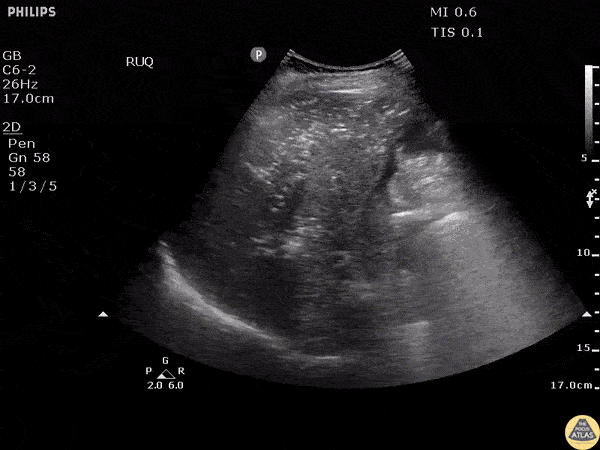

An adult male presented to the ED with abdominal pain and hypotension. The perihepatic window of the RUSH exam reveals portal venous gas due to necrotizing pancreatitis. Also, note the trace free fluid in Morison’s pouch. Image courtesy of Robert Jones DO, FACEP @RJonesSonoEM Director, Emergency Ultrasound; MetroHealth Medical Center; Professor, Case Western Reserve Medical School, Cleveland, OH View his original post here